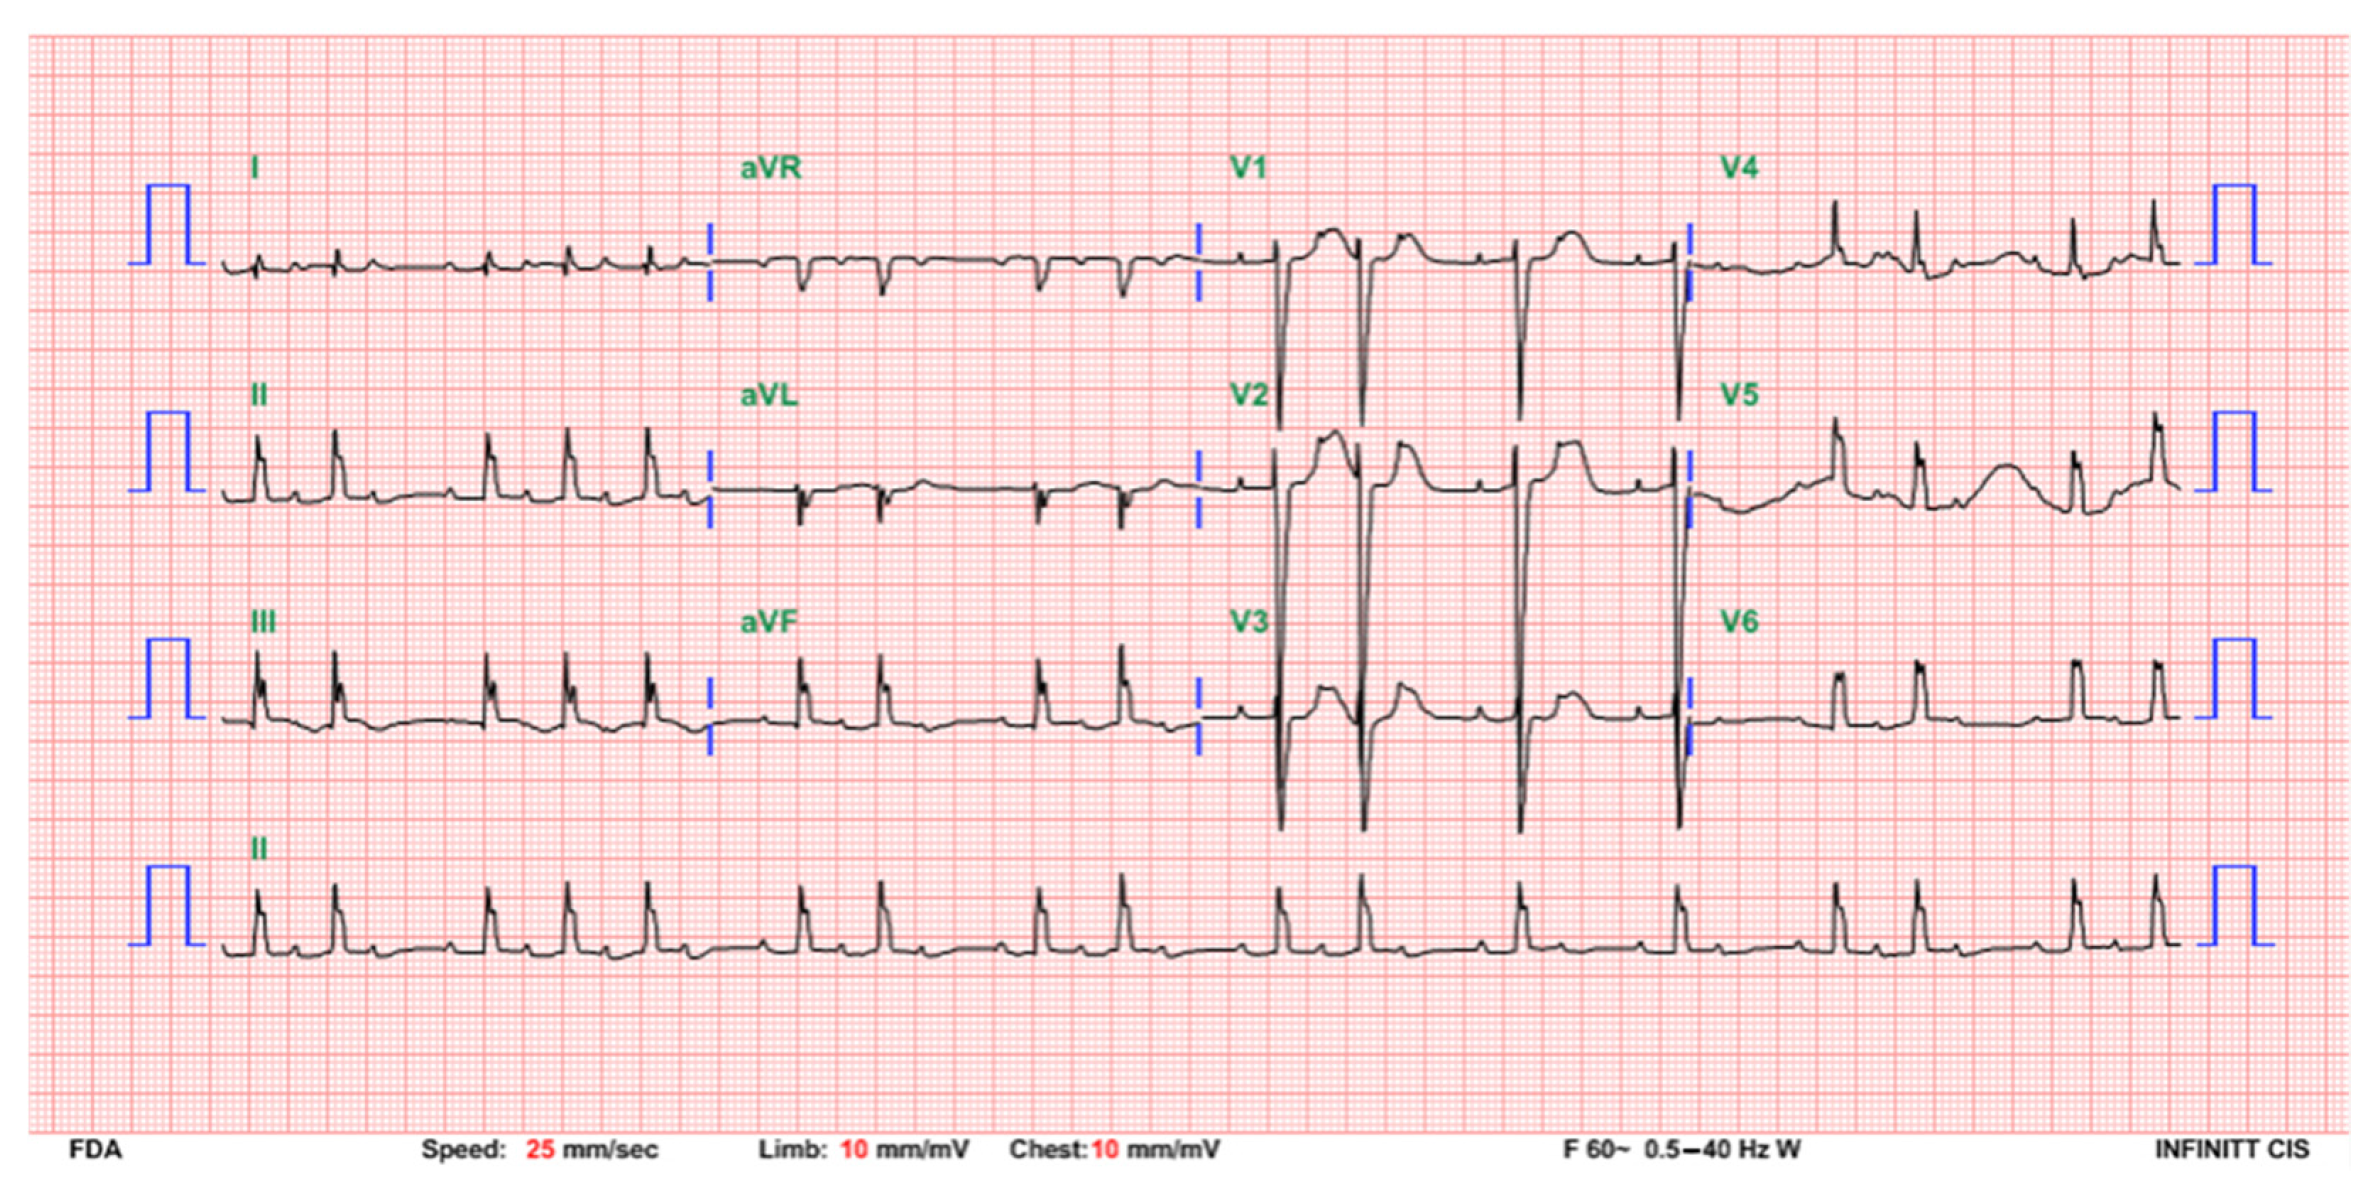

Figure 1.

A postdelivery ECG indicating a complete AV block with an atrial rate of 158 beats per minute and a ventricular rate of 75 beats per minute.